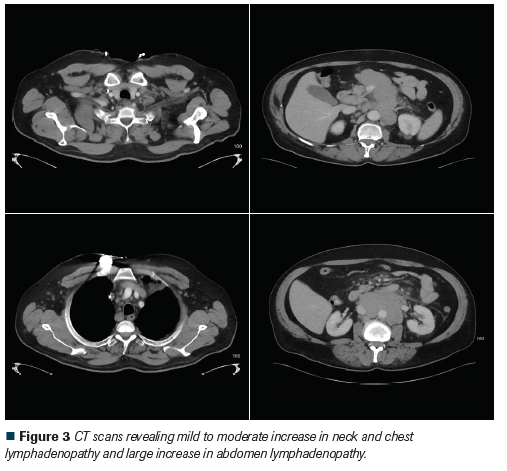

Figure 3 CT scans revealing mild to moderate increase in neck and chest lymphadenopathy and large increase in abdomen lymphadenopathy

Six months into his continued treatment with ibrutinib, the patient developed mild mental confusion, anorexia, and abdominal pain. Further evaluation revealed an elevated serum calcium level of 17.3 mg/dL, and CT scans revealed a mild to moderate increase in neck and chest lymphadenopathy and a large increase in abdomen and pelvis lymphadenopathy (Figure 3). A biopsy of a para-aortic node showed lymphoid tissue with B-cell CLL/SLL (Figure 4). The majority of cells in the biopsy specimen were small to intermediate in size with some scattered large cells. There were several areas with prolymphocytes and paraimmunoblasts consistent with proliferation centers. He was started on venetoclax (Venclexta)4 and had a short-lived clinical response lasting 1 month. Coincidentally, with disease progression, hypercalcemia reappeared. A bone marrow biopsy showed hypercellular bone marrow with atypical lymphoid proliferation with large cells concerning for Richter’s transformation (Figure 5). He was evaluated for chimeric antigen receptor T-cell therapy; however, his underlying disease progressed rapidly. The patient and family decided on hospice care. His overall condition deteriorated with persistent refractory hypercalcemia and he passed away shortly thereafter.